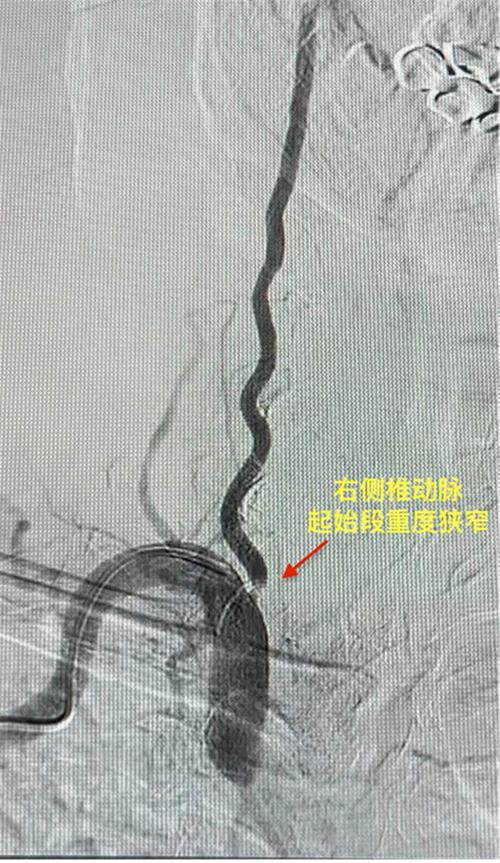

内江市市中区人民医院完成首例椎动脉狭窄支架植入术

微甜城

|

2024/02/22 17:46

1674点击